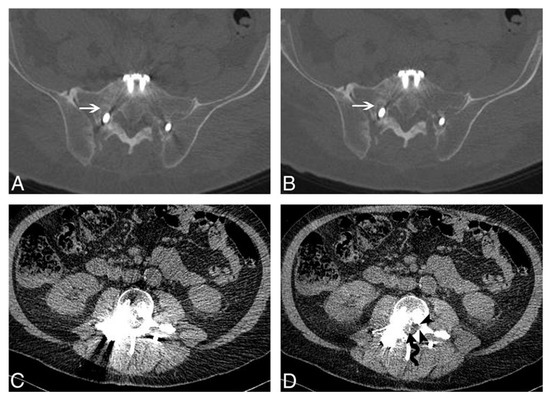

Radiological Classification and Management Algorithm of Petrous Apex Cholesterol Granuloma

Background: Petrous apex cholesterol granulomas (PACGs) are benign inflammatory cystic lesions of the temporal bone. Usually, asymptomatic patients may develop symptoms as the lesions expand. The diagnosis is based on both CT and MRI scans and the management relies on “wait and [...] Read more.

Background: Petrous apex cholesterol granulomas (PACGs) are benign inflammatory cystic lesions of the temporal bone. Usually, asymptomatic patients may develop symptoms as the lesions expand. The diagnosis is based on both CT and MRI scans and the management relies on “wait and scan” or surgery. This paper aims at evaluating surgical outcomes and proposing a CT-based classification and a management algorithm. Methods: Patients with PACGs who were surgically treated between 2014 and 2024 were included. Symptoms, imaging, approach type and complications were considered. CT scans were classified as Type A (preserved apex cellularity), Type B (erosion of the apex cellularity), and Type C (involvement of the noble structures bone boundaries). The possible connection of the lesion with the infracochlear, perilabyrinthine and sphenoidal cellularity was assessed. Results: Nineteen patients with symptoms like diplopia, headache and sensorineural hearing loss were included. According to our classification, 1/19 patients was Type A, 4/19 were Type B and 14/19 were Type C. Five patients underwent a total resection, seven a subtotal and seven a surgical drainage. Only two complications were recorded, and 17/19 patients showed symptom regression and stability during follow-up. Conclusions: While the management of PACGs is still controversial, according to our classification and surgical outcomes, Type A, being mostly asymptomatic, should be managed with “wait and scan”, Type B should undergo surgery when symptoms are present, while Type C should always undergo surgery because of their invasiveness and potential complications. When possible, a drainage should be attempted; otherwise, a surgical resection is chosen, and its completeness depends on the preoperative general and hearing status. Full article